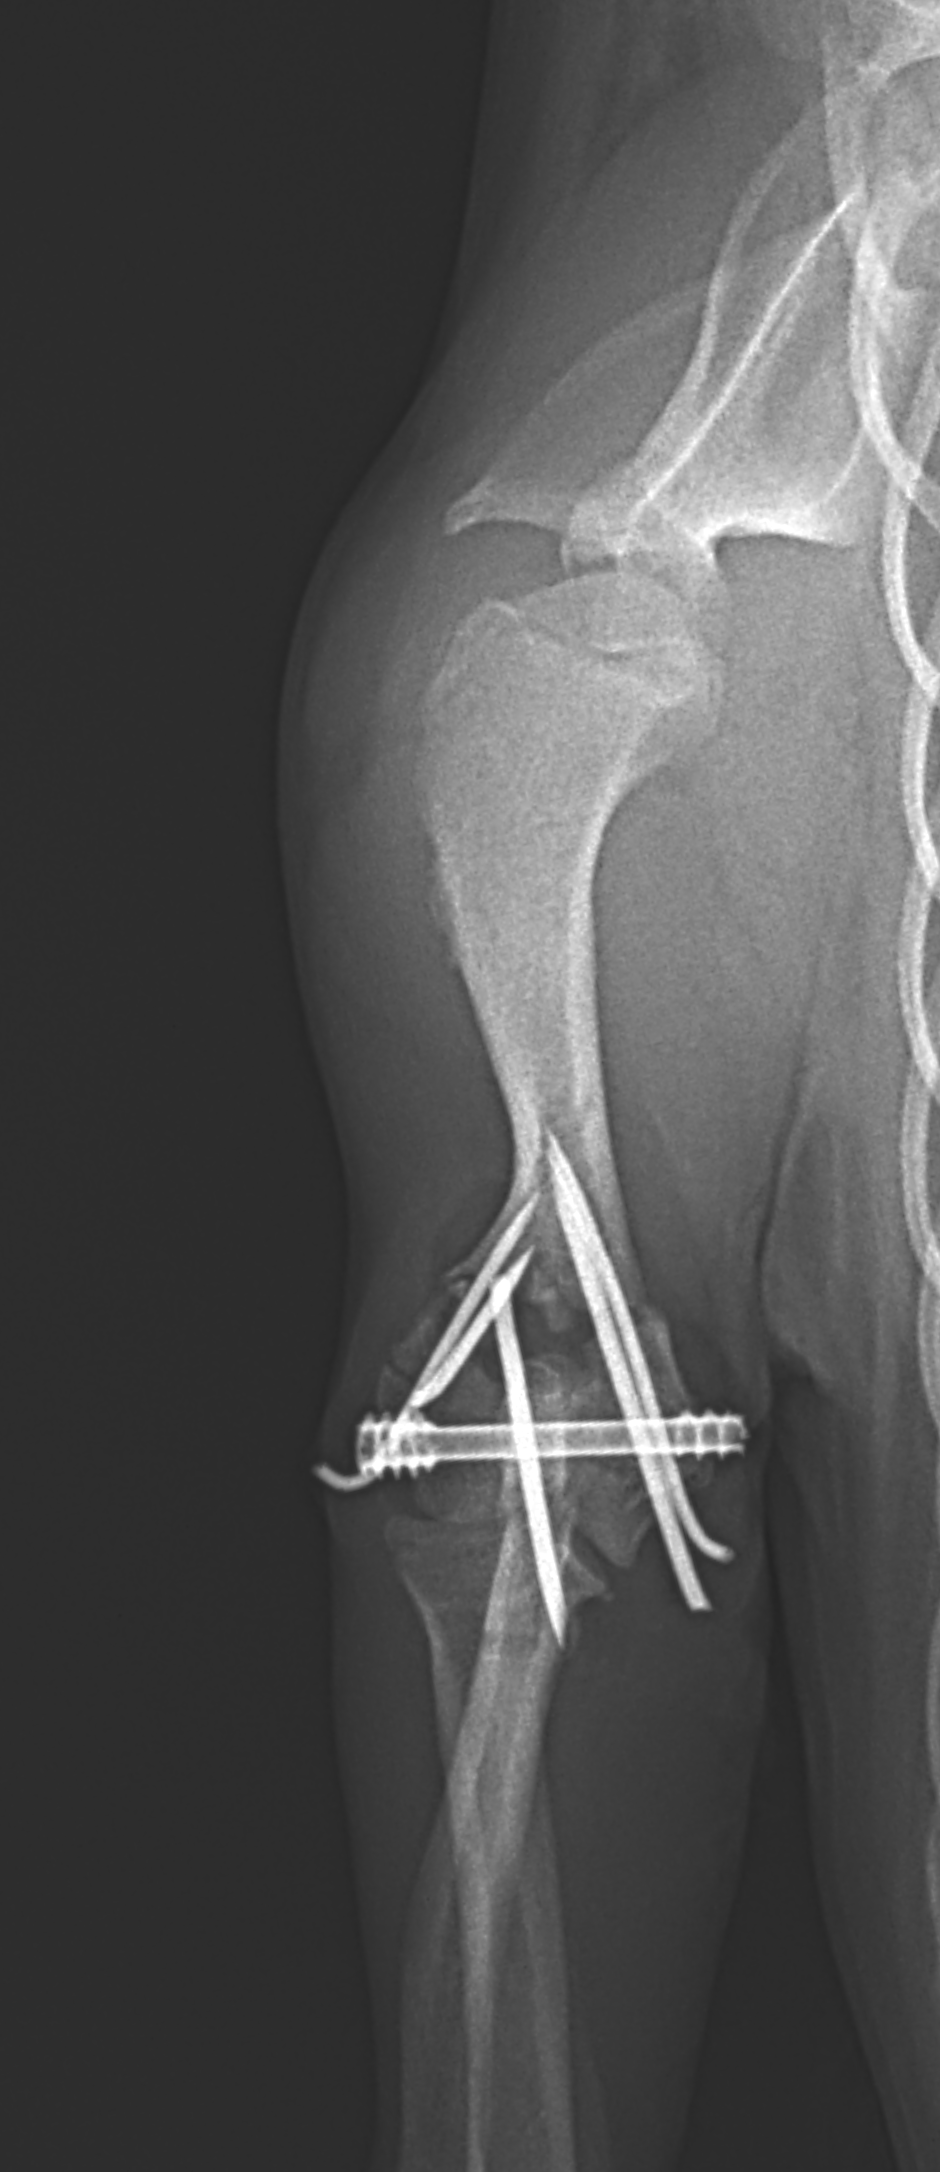

超小型犬に対する上腕骨遠位Y字骨折

4ヶ月齢 体重1.2kgの極小犬に発生した上腕骨遠位Y字骨折に対し、2.4mmキャニュレイティッド・ヘッドレス・コンプレッションスクリューを用いた整復固定を実施しました。(Rita LeiCOM cannulated compression screw) 患者さんの骨格は非常に小さく、最小侵襲かつ関節面の解剖学的整復を重視し、ガイドワイヤーを用いた正確なスクリュー挿入により圧迫固定を行いました。術後は良好なアライメントを維持し、関節機能の温存が期待される結果となっています。極小犬の関節内骨折においては、インプラント選択と精度の高い操作が予後を大きく左右することを改めて実感する症例でした。